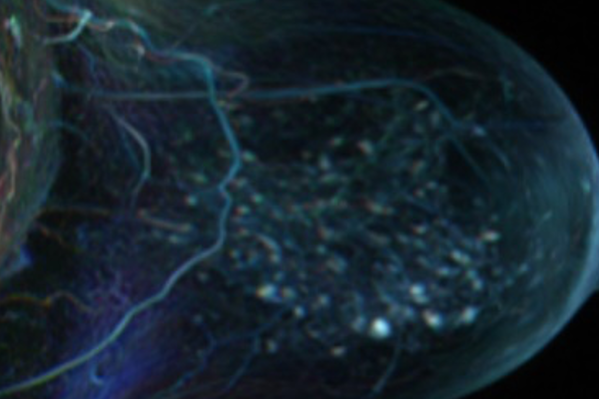

PREDICTOME

PREDICTOME (Start 2021) develops machine learning models for the prediction of response to neoadjuvant chemotherapy in breast cancer. It analyses the dynamics of early treatment response in imaging data and epigenomics profiles to understand their relationship and predictive value. It is funded by the WWTF.